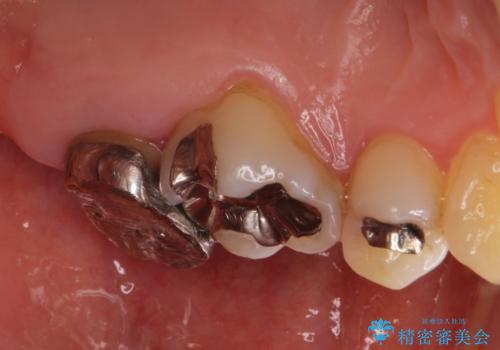

- 奥の銀歯を白くしたいとの事で来院。

痛みはないとの事でしたがレントゲンを撮影したところ根の先に病巣がある事がわかりました。

被せ物、古い材料を徹底的に除去し、ラバーダム防湿にて無菌的処置を行い、セラミックの被せ物で治療を行いました。